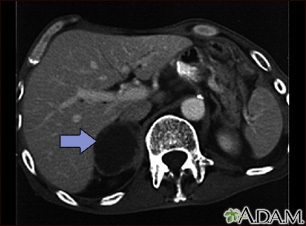

- Abdominal CT scan

- MRI of abdomen